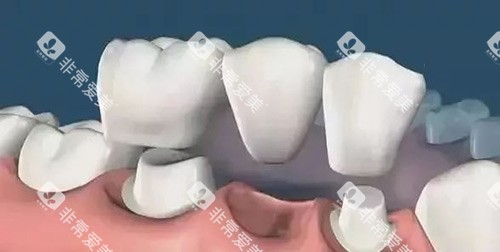

2. 固定义齿:性价比高

"把两边好牙磨小当'桥墩',中间架个烤瓷牙。"上海九 院程蕙娟副主管医师指着模型解释。这种方案适合邻牙健康、咬合空间够的情况。35岁的白领张女士刚做完:"虽然要磨掉点牙釉质,但戴上后跟真牙差不多,吃排骨都没问题!"价格方面,普通烤瓷牙每颗1500元起步,全瓷牙得3000元起以上,具体要看材料品牌。